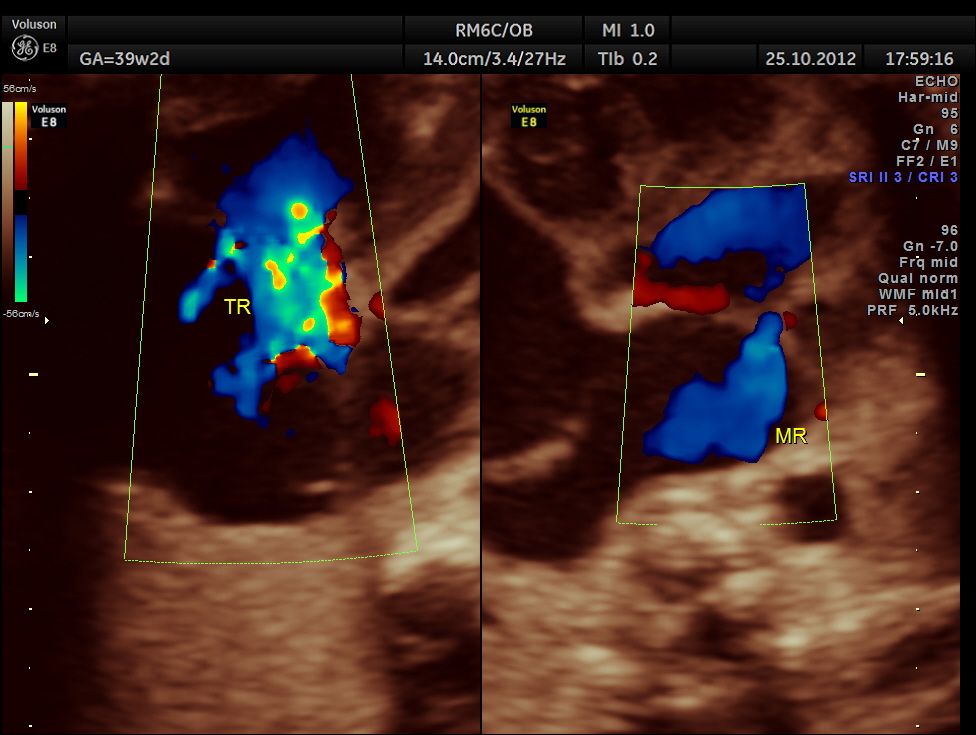

THIS FETUS HAD SEVERE FETAL ANEMIA WITH CARDIAC FAILURE LEADING TO CARDIOMEGALY WITH MITRAL, TRICUSPID AND PULMONARY REGURGITATION .NO OTHER OBVIOUS CARDIAC ANOMALY WAS MADE OUT . THE VENO ATRIAL , ATRIO VENTRICULAR AND VENTRICULO ARTERIAL CONCORDANCE APPEARED TO BE NORMAL; NO SEPTAL DEFECT WAS MADE OUT.